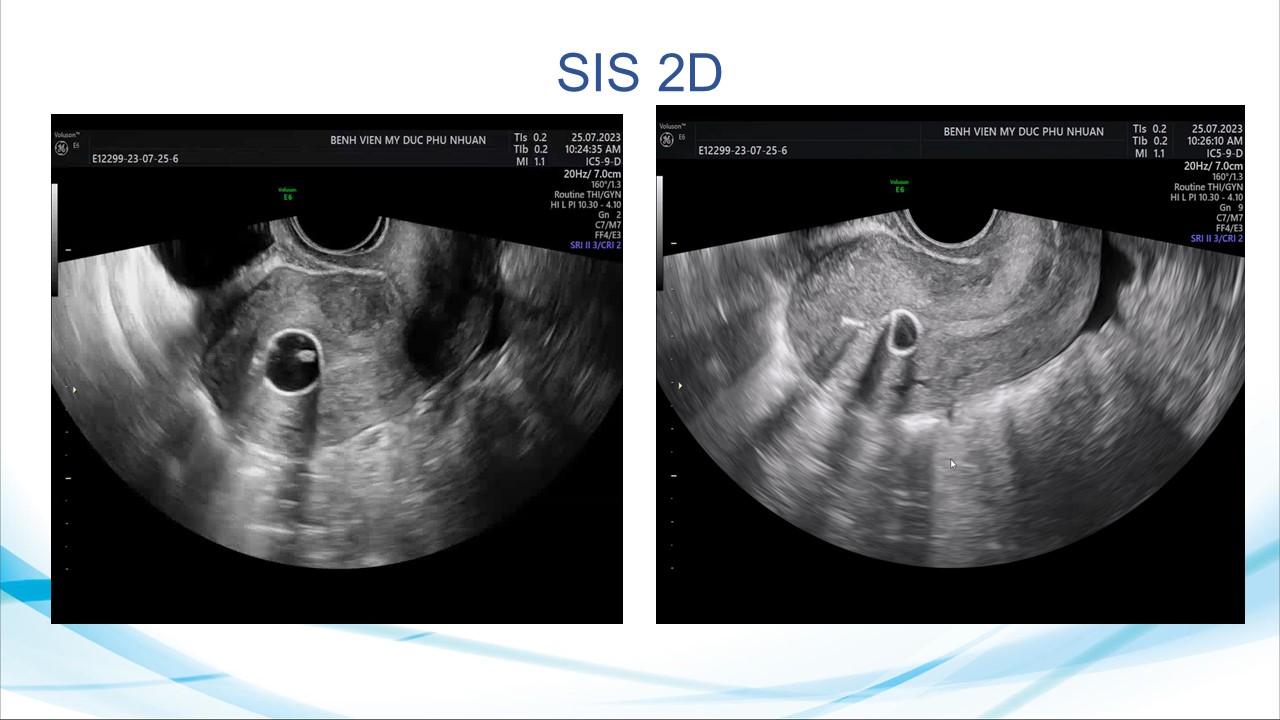

Siêu âm sử dụng chật tương phản trong phụ khoa